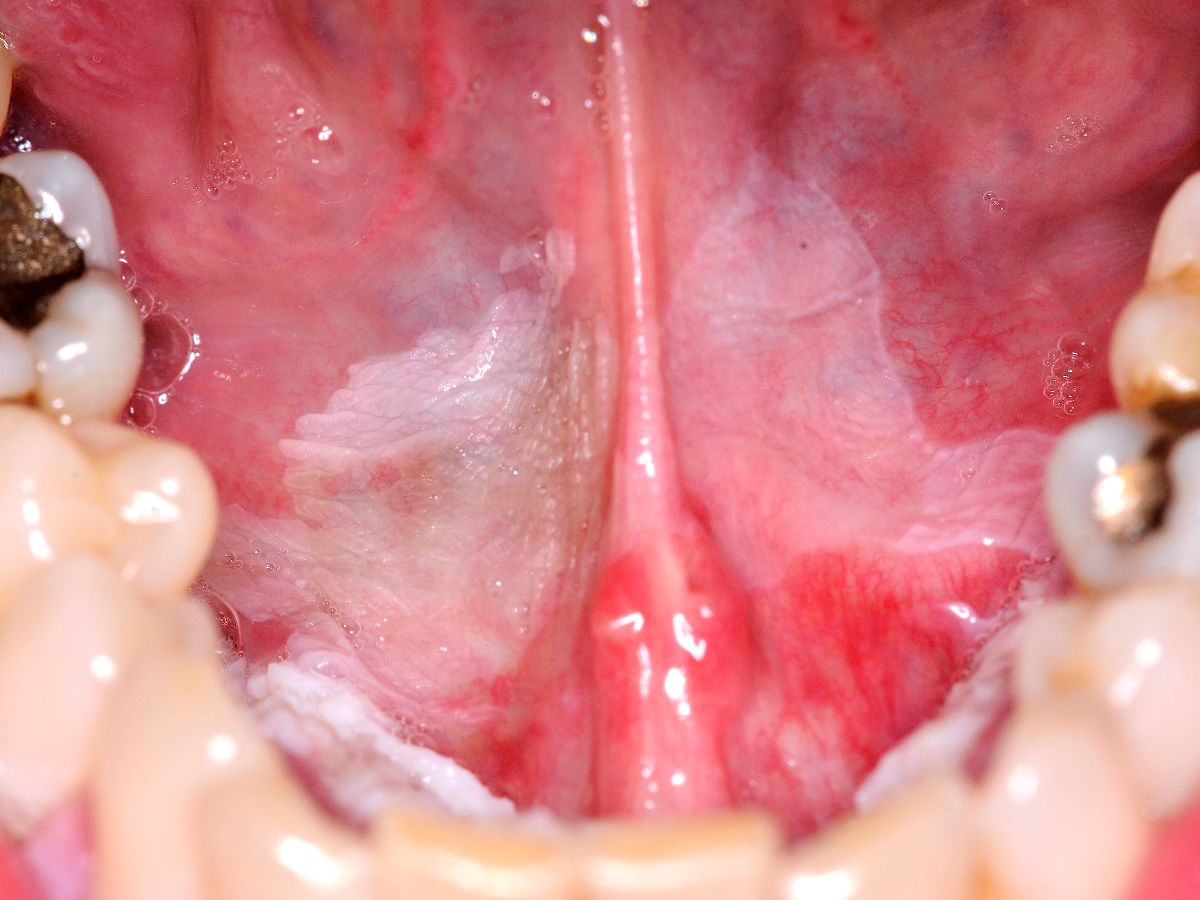

Orale leukoplakie is een witte verkleuring en verandering van het mondslijmvlies. Het komt vaak voor (bij circa 13% van de bevolking kunnen witte verkleuringen worden aangetroffen). Leukoplakie is een beschrijvende diagnose, het histologisch beeld van leukoplakie kan variëren van hyperkeratose met of zonder epitheeldysplasie, via carcinoma in situ en micro-invasief carcinoom tot invasief carcinoom. Klinisch worden er 2 varianten onderscheiden: homogene en niet-homogene leukoplakie. Homogene leukoplakie is een egaal witte verkleuring met een vlak, dun en glad oppervlak. Niet-homogene leukoplakie is een witte of witrode afwijking die irregulair vlak, nodulair of exofytisch kan zijn. Het homogene type is vaak asymptomatisch, terwijl het niet-homogene type gepaard kan gaan met pijn of hinder. Orale leukoplakie kan overgaan in een carcinoom van de mondholte; 17-35% van de carcinomen ontstaan uit preëxistente afwijkingen, vaak leukoplakie. Leukoplakie komt ook voor op andere slijmvliezen (leukoplakie van de penis of de vulva).

Leukoplakie kan worden veroorzaakt door externe factoren zoals roken, mechanische irritatie, candida. In dat geval kan het verdwijnen door die factoren weg te nemen. Indien het na 2-4 weken niet is verdwenen dan gaat het om echte leukoplakie, en is er kans op epitheeldysplasie: het advies is om een biopt af te nemen.

De mate van dysplasie wordt onderverdeeld in gering, matig en ernstig. Er is een direct verband tussen de mate van dysplasie en de kans op maligne ontaarding. De kans op maligne ontaarding binnen 5 jaar is ongeveer 5%. Het ontstaat vooral in niet-homogene leukoplakie.

Risicofactoren voor het ontstaan van leukoplakie zijn roken, alcoholgebruik, Candida infectie, HPV infectie, deficiënte voeding (vooral tekort aan vitamine A, B12, C, beta-caroteen, foliumzuur). Leukoplakie ontstaat meestal vanaf 30 jaar, de meesten zijn ouder dan 50 jaar. De kans op maligne ontaarding is verhoogd bij aanwezigheid van één van de volgende kenmerken: epitheeldysplasie in het biopt; niet-homogene type; vrouwelijk geslacht; langer bestaande leukoplakie; leukoplakie bij niet-rokend persoon; locatie in de mondbodem of op de tong; aanwezigheid van C. albicans.